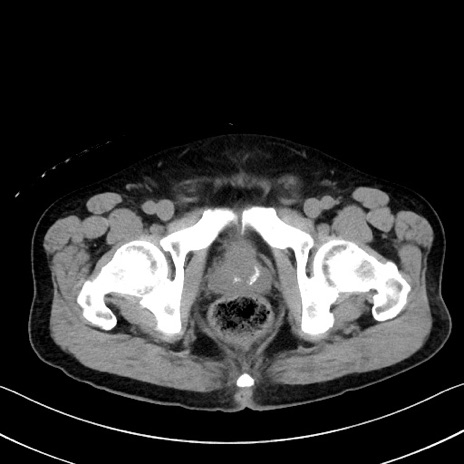

冠状断像

【症例】70歳代 男性

【主訴】腹部膨満、嘔吐

【現病歴】昨日より腹部膨満感出現。本日増悪し、仙痛出現。嘔吐あり、受診。

【既往歴】糖尿病、胆摘後

【身体所見】BP 149/80mmHg、HR 74/min、BT 35.9℃、腹部:膨満、軟、圧痛なし。腸雑音減弱あり。上腹部正中切開瘢痕あり。

【データ】WBC 13500、CRP 1.72